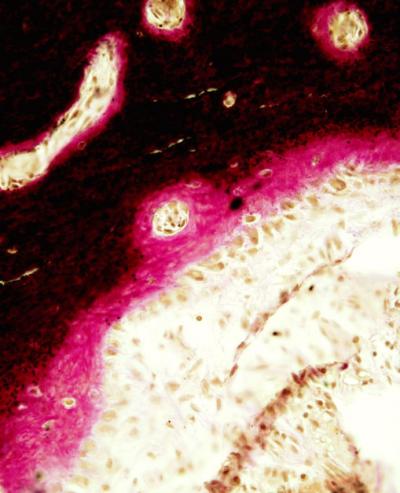

To investigate the molecular pathology of NF1, Elefteriou and his colleagues, including first author Jean de la Croix Ndong, Ph.D., have studied a mouse model of the disorder. They noticed in histological stains of bone tissue that the mice had an accumulation of non-mineralized matrix, a condition called hyperosteoidosis.

They have now discovered that hyperosteoidosis in the mice is caused by accumulation of the molecule pyrophosphate, a strong inhibitor of bone mineralization. They found that in the absence of neurofibromin, the expression of certain genes is upregulated. These include genes that enable increased production and transport of pyrophosphate and a gene that prevents calcium and phosphate from depositing on collagen fibers.